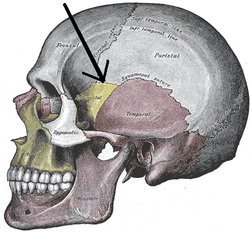

Side view of the skull with arrow pointing to the Pterion | |

The pterion is the region where the frontal, parietal, temporal, and sphenoid join together.[1] It is located on the side of the skull, just behind the temple.

The pterion is located in the temporal fossa, approximately 2.6 cm behind and 1.3 cm above the posterolateral margin of the frontozygomatic suture.[2]

It is the junction between four bones:

- the parietal bone

- the squamous part of temporal bone

- the greater wing of sphenoid bone

- the frontal bone

These bones are typically joined by three cranial sutures:

- the sphenoparietal suture joins the sphenoid and parietal bones

- the coronal suture joins the frontal bone to the sphenoid and parietal bones

- the squamous suture joins the temporal bone to the sphenoid and parietal bones